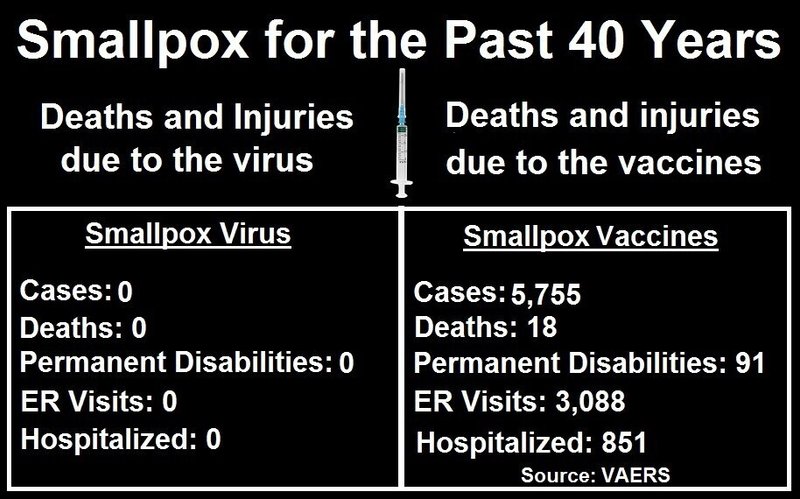

天然痘による死傷者数は40年間でゼロ、しかし天然痘ワクチンによる死傷者数は5,755人

天然痘ワクチンはすでに存在しているので、政府のVAERS(ワクチン有害事象報告システム)データベースで、天然痘ワクチン接種後にどれだけの怪我や死亡が報告されているか調べてみました。天然痘は、米国ではもう40年以上根絶されたと言われており、過去40年以上の間に死亡や怪我に至った事例は知られていないからです。

天然痘ワクチンは、もはや米国には存在しない病気に対して、18人の死亡、91人の後遺症、3,088人の救急室への受診、851人の入院を含む5,755件の訴訟を起こしています(Source)

つまり、天然痘ワクチンによる怪我や死亡の報告は、過去40年以上の間に接種されたごく少量の天然痘ワクチンによるものであるらしい。